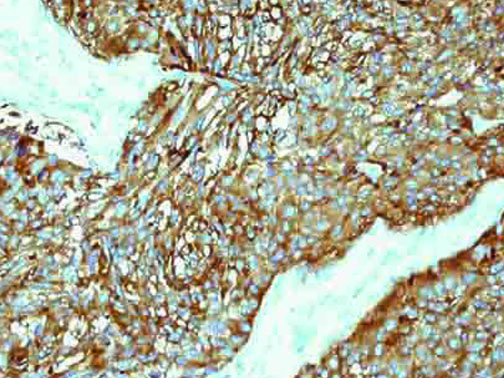

It is the ICU physician who is most likely to witness one of the deadliest manifestations of the abnormal immunological response, the cytokine storm syndrome (CSS). This response is also referred to by some as the cytokine release syndrome (CRS). CSS is characterized by continuous activation and expansion of macrophage and lymphocyte populations, which secrete large amounts of cytokines, causing the cytokine storm. This massive cytokine release is akin to hemophagocytic lymphohistiocytosis (HLH) disease, a syndrome characterized by initial unchecked and persistent activation of cytotoxic T lymphocytes and NK cells.

Clinical and laboratory manifestations of HLH include fever, enlarged liver and/or spleen, neurologic dysfunction, coagulopathy, liver dysfunction, cytopenias (i.e., low levels of erythrocytes, leukocytes, and/or platelets), hypertriglyceridemia, hyperferritinemia, hemophagocytosis, and eventually diminished NK cell activity as the immune system becomes progressively paralyzed. HLH can be familial (primary HLH) or secondary to another disease process (sHLH), such as rheumatic disease, in which it is referred to as macrophage activation syndrome (MAS, characterized by elevated ferritin).